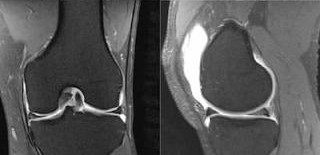

МРТ (магнитно-резонансная томография) применяется в случаях, когда требуется:

• оценить состояние хряща на ранних стадиях гонартроза

• выявить повреждения менисков и связок

• определить изменения мягких тканей и синовиальной оболочки

• уточнить причину боли при недостаточной информативности рентгена

МРТ позволяет детально визуализировать внутрисуставные структуры, а КТ — получить точную информацию о состоянии костных элементов сустава.